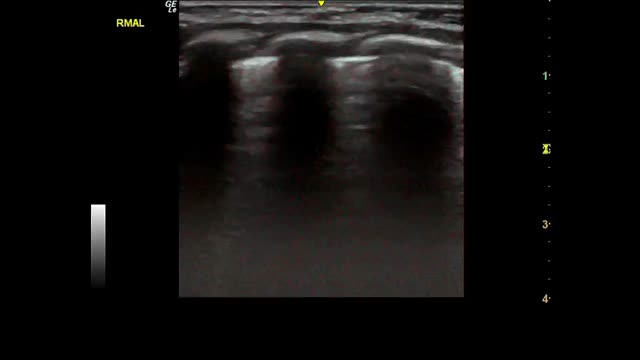

Most of the studies under analysis had LU findings in common in the presence of SARS-CoV-2 infection. The most common finding was B lines, which had very distinct characteristics, 34 of which reported focal, diffuse and confluent B lines.12,15,18,19,25,26,27,29,30,31,32–35,38,62,67,68,70,72–74,77–88 Twenty-nine studies described consolidations of different types: small, large, linear, subpleural, multifocal and translobar,12,15,18,19,25,26,27,29,30,33,35,38,62,63,67,68,70,72,73,75,78–80,82–85,87,89 associated with white lung12,30 and with air bronchograms18,38. Nineteen studies described pleural irregularities,12,15,18,26,27,30,32,33,35,62,70,72,77,79,80,82,84,85,89 and 19 reported pleural and subpleural line alterations, such as thickening or shred sign.18,19,26,29,31,32,34,38,62,67,70,72,73,75,77,80,85 Ten studies referred to pleural effusion,38,62,67,70,72,75,77,82–84 8 reported bilateral findings15,34,63,79,82,86,87,88 and 3 revealed preponderance of compromise in posterior areas.79,80,89 Three studies associated appearance of A lines during recovery 35,67,80 and most of the papers reported the LU role in the serial evaluation of patients with COVID-19.27,29,30,33,35,67,68,70,71,72,74,75–77,80

Eighteen studies used LU scores.12,38,62–64,67–71,74–77,79,80,82,87 One study proposed a unified approach to standardize the use of LU in the clinical management of patients with COVID-19,12 with a score system to classify the seriousness of the lung disease (score): (0 points) presence of A lines with continuous and regular pleural line; (1 point) presence of visible B lines and irregularities in the pleural line; (2 points) presence of discontinuous pleural line with dark areas under the pleura (consolidations) with associations of B lines; (3 points) presence of coalescent B lines with “white lung” aspect, dense and widely distributed, with or without consolidations. In that study, 14 thoracic regions were evaluated, using a LU score from 0 to 42 points, in which higher score represented higher severity. Another study38 applied an LU scoring method ranging from 0 to 36 points in which both hemithoraces were divided into six regions (totaling 12 areas) where: (0) points = presence of pleural line and A-line, <3 B-lines; (1) point = presence of more than 3 B-lines; (2) points = presence of coalescent B-lines; (3) points = presence of pulmonary consolidation signs. The same assay presented a classification of severity of lung lesions: none (0 points); mild (1–7 points); moderate (8–18 points), severe (≥19 points).40 A third assay showed a scoring system of three items: (a) pleural line involvement, where (0) points = normal; (1) point = thickening (≥0.5 mm) or irregular; (2) points = blurred; (3) points = discontinuous, fragmented; (b) lung parenchymal involvement, where (0) points = no B-line; (1) point = presence of B-line ≤3; (2) points = presence of B-lines ≥4 or partially merged; (3) points = presence of B-line fully integrated (white lung or waterfall sign); (4) points = presence of pulmonary consolidation or subpleural lesion; (c) complications, where (0) points = none; (4) points = am line (pulmonary balloon); (4) points = pneumothorax or empyema; (4) points = pleural effusion. Pleural line, pulmonary parenchyma and complications were observed and scored respectively in each of the 10 examined sections.62 Also, Zhao et al. proposed a scoring system from 0 to 4 points imputed to 10 lung sonographic areas, as described below: (0) points = presence of normal pattern with lung sliding, parallel A-lines and thin pleural line; (1) point =presence of B-lines pattern; (2) points = presence of ground glass sign with B-lines occupying the entire screen; (3) points = presence of shred sign suchlike small subpleural consolidations; (4) points = presence of consolidation/pulmonary tissue-like aspect or pleural effusion.67

Fig. 2 shows the main findings of the LU imaging described in the study.